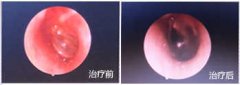

胆脂瘤型中耳乳突炎必须做手术吗 治疗案例

患者自幼双耳廓畸形,与人交谈困难。2年前出现左耳流黄色脓性分泌物并反复发作,分泌物有异味。伴有耳痛,呈持续性胀痛。半月前左耳后皮肤红肿,瘘口处有脓液。近一个月来患者自觉右耳听力比以前有下降。... [详情] 文章日期 :17-07-05